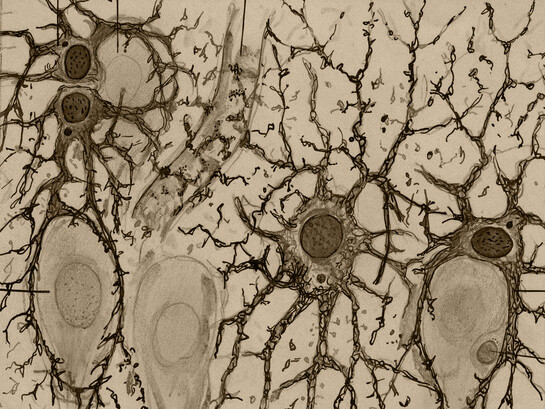

(Célula glial, ilustración de Santiago Ramón y Cajal – detalle)

Allí se dedica a consolidar su obra sobre el sistema nervioso, basándose en dos elementos con los cuales ha venido trabajando: el trabajo sobre el embrión en vez del adulto y el mejoramiento que ha realizado del método tintorial de Golgi, «el de la doble impregnación».

Y así surge resplandeciente en su microscopio, la unidad fundamental del sistema nervioso: «la célula que Waldeyer bautizará con el nombre de neurona» (Pollack, K.).

(Astrocitos del hipocampo del cerebro humano, ilustración de Santiago Ramón y Cajal-detalle)